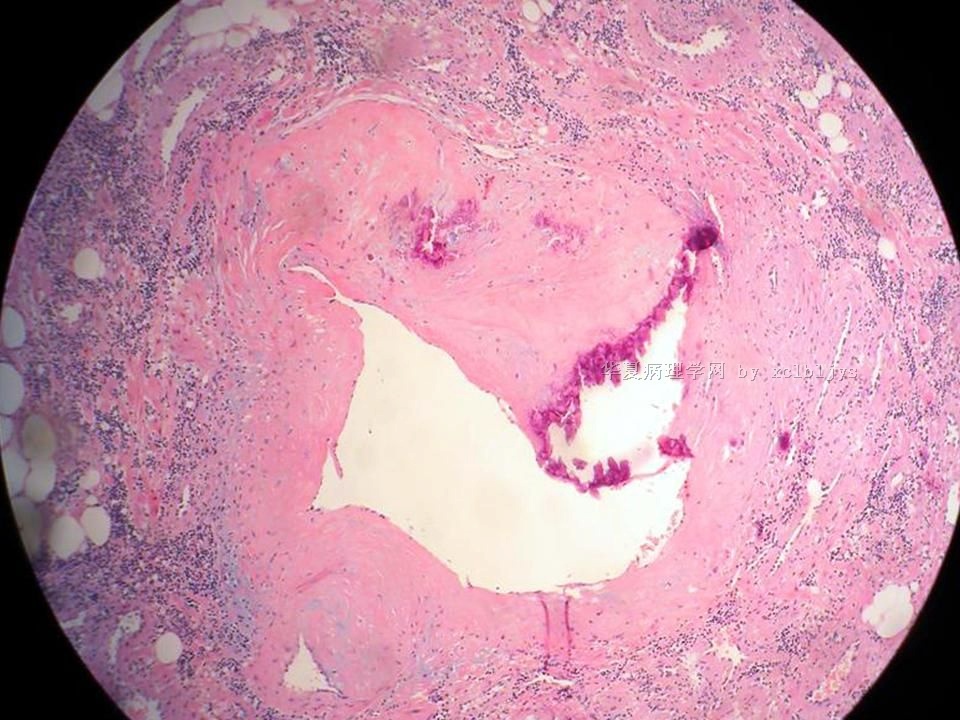

| 以下是引用xclbljys在2010-12-22 17:20:00的发言: 本例我们科室医生有两种意见:一种是炎性假瘤;第二种意见是炎性假瘤伴局限性Wegener肉芽肿。 依据是眼眶内肿块含有大量的动脉内膜炎改变,浸润的炎细胞有淋巴细胞、浆细胞、嗜中性粒细胞和嗜酸细胞等,如图16所示,炎细胞已经浸润动脉壁全层,应符合坏死性小动脉炎,但尚不能确定动脉壁弹力纤维层的破坏。 请各位老师点评! Wegener肉芽肿多发生在上呼吸道、肺、肾脏和皮肤等器官与组织。坏死性血管炎需证实有纤维素样坏死。小动脉炎多在皮肤病变比较明显。本例的小动脉炎或许是炎症引起的继发性改变。需要完善病史,查血免疫指标,看有没有系统性疾病。如果没有系统性疾病,还是考虑慢性炎症继发小血管炎。

血管炎是正常营养/供给血管的炎症性病变,而不是增生血管的炎症。血管炎往往有明显的临床相应症状,如皮疹。典型的Wegerner肉芽肿病有三联症(上呼吸道、肺、肾脏病变)。血管炎不仅是有炎症细胞,同时有血管壁的变性、坏死(纤维素样), 内皮细胞的变质和增生,炎症细胞浸润(包括中性粒细胞、淋巴细胞、组织细胞、嗜酸性细胞、巨细胞等)。不同类型的血管炎累及的血管大小、炎症细胞的类型、有无肉芽肿改变都不相同。血管炎的病因可以是过敏、自身免疫、胶原性疾病、感染等多种因素。